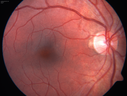

16 year old with incidental finding of retinal AV malformation but vision in the left eye is not as good as the right eye. VA OD: sc20/16 NscJ1+ VA OS: sc20/20-1 NscJ1+